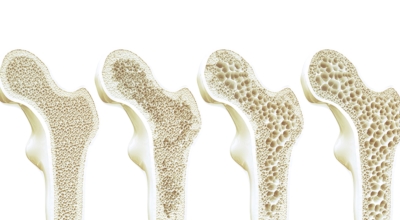

중년에 접어들면 뼈에 좋은 칼슘제과 관절영양제를 찾게 됩니다. 영양제도 좋지만 뼈와 관절에 좋은 운동과 식이요법도 중요해요. 뼈에 이상이 생기면 골다공증으로 이어지므로 특히나 관리를 잘 해야 해요. 일반적인 때에 음식을 통해 어떻게 관리를 하면 되는지 골다공증에 좋은 음식을 알려드리려고 해요.

골다공증 예방이나 고치기 위해 뼈 건강에 해가 되는 음식들의 섭취는 제한해야 해요. 탄산음료나 술, 카페인 음료, 지나친 동물성 단백질 섭취 등은 골다공증을 악화시킬 수 있기에 조심하시는 게 좋을 것 같아요.

골다공증에 좋은 음식에 대하여 알아봤어요. 참고하셔서 더 좋은 삶을 위해 힘써보시기 바랄게요.